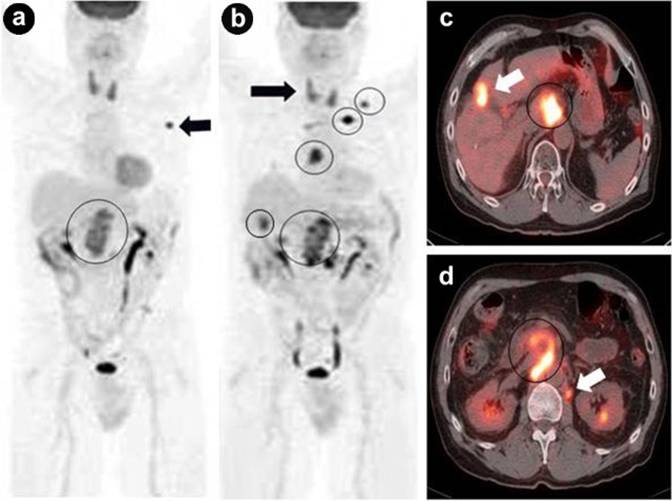

PET/CT in Post-Therapeutic Monitoring

Preliminary evidence indicates that PET/CT is useful to distinguish recurrent/residual hypermetabolic malignancy from post-surgical changes/fibrosis in the pancreatic fossa, to characterize the metabolic behavior of non-specific hepatic lesions too small or not accessible for biopsy, to restage cases presenting with rising tumor marker levels and negative CT evaluation, and to assess the tumor response to neoadjuvant therapy [1]. Two examples are seen in Figures 2 and 3.

|

Figure 2. a. Coronal PET maximum intensity projection image shows hypermetabolic lesion of the head of the pancreas (circle) with a few hepatic metastases (arrowheads). b. Fused axial PET/CT image reveals the corresponding hypermetabolic pancreatic malignancy (crosshair). c. Post-therapeutic PET monitoring image demonstrates worsening with persistent pancreatic mass (circle), diffuse hepatic, and peritoneal metastases (arrowheads). |

Figure 3. a. b. Serial coronal PET maximum intensity projection images show poor therapeutic response with disease progression at the pancreatic fossa, peripancreatic nodes, liver, mediastinum, left supraclavicular node, and left lung apex (circles). Two incidental findings: diffuse thyroid uptake from thyroiditis and left axillary uptake from left upper extremity tracer injection infiltration (black arrows, potential false-positive PET findings). c. Corresponding fused axial PET/CT image shows hypermetabolic lesion of the head of the pancreas (circle) with liver metastasis (white arrow, also seen on the middle coronal PET maximum intensity projection (b.)). d. Another corresponding fused axial image reveals lesion of the uncinate process (circle) with retroperitoneal nodal metastasis (white arrow). |